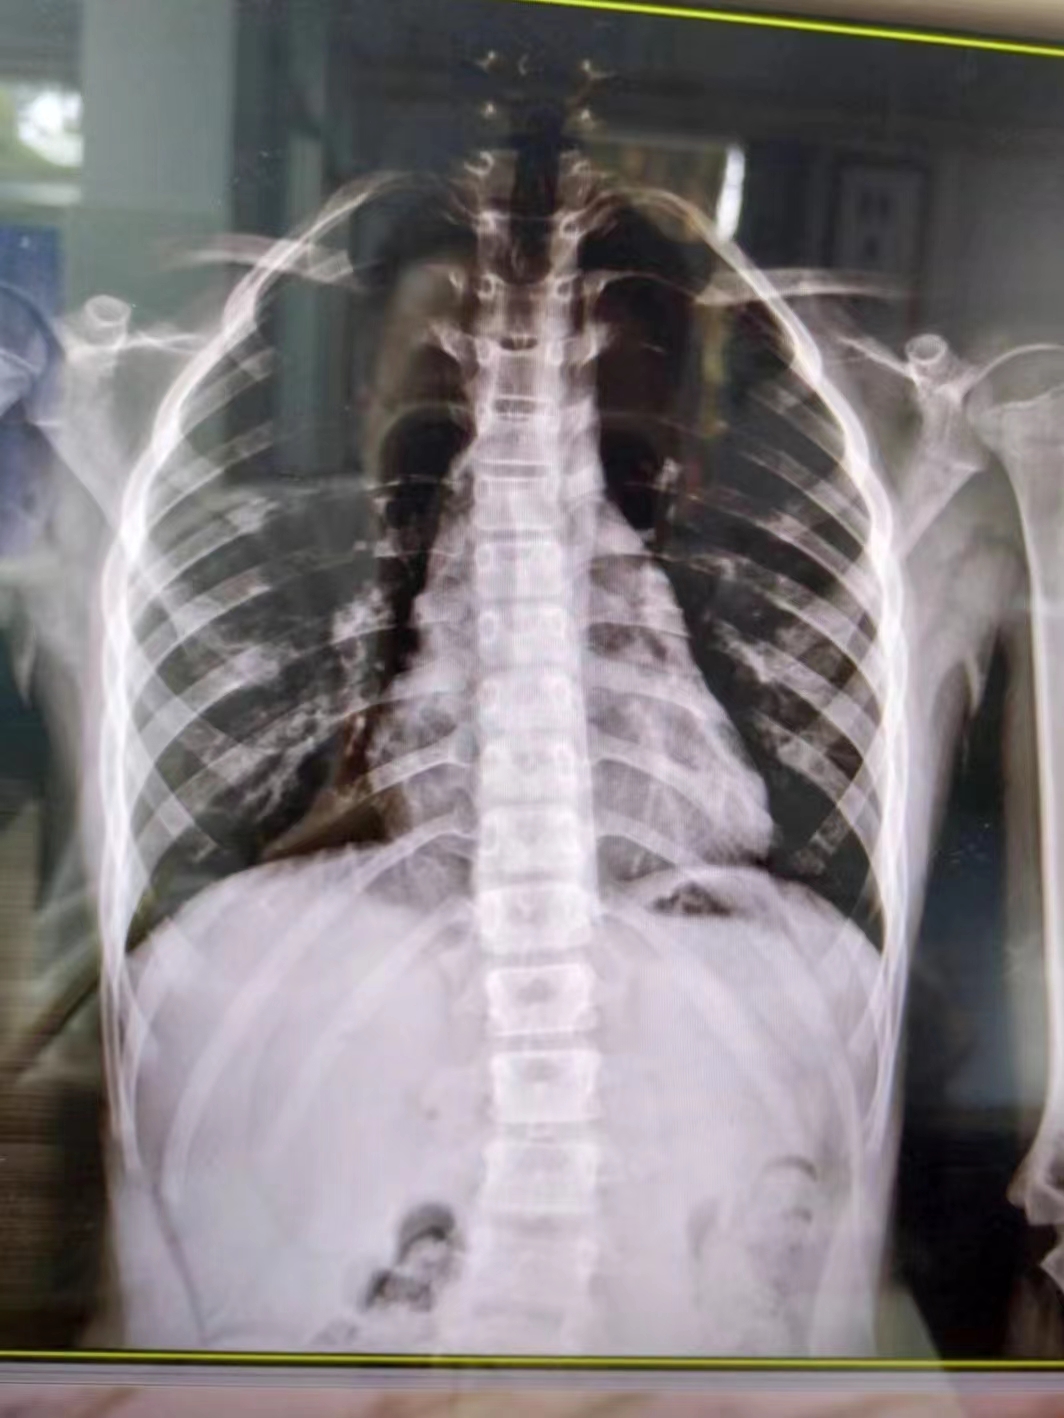

在康復(fù)醫(yī)學科,徐棟醫(yī)生通過X線片確認小朋友患有脊柱側(cè)彎,“其實肉眼也可以看到小朋友的脊柱有彎曲弧度,家長的擔心是正確的?!?/p>

幸運的是,由于媽媽發(fā)現(xiàn)及時,小朋友的情況無需手術(shù)治療,經(jīng)過7次整脊手法按摩治療后,側(cè)彎明顯好轉(zhuǎn)。